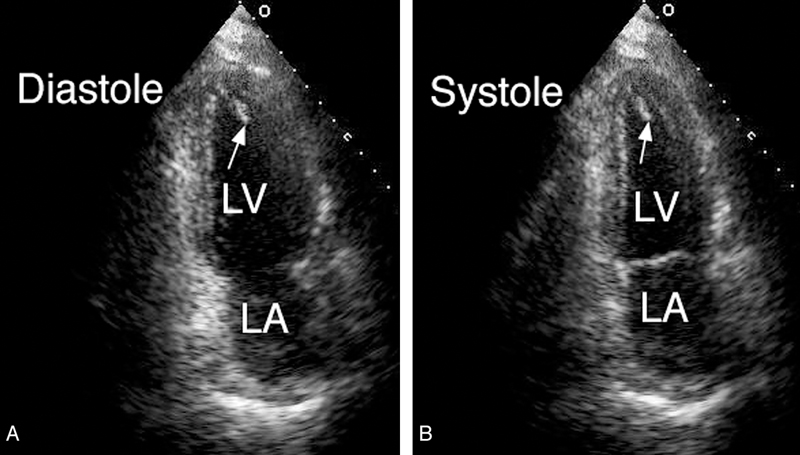

فحوصات تشخيصية لبعض امراض القلب والشرايين التاجية